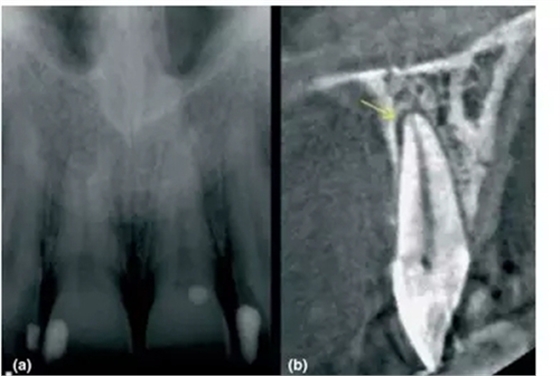

a- 右上2的金屬充填體導致圖像出現(xiàn)散射和射線硬化;

b- 當散射影像與牙釉質(zhì)重疊時,容易被誤診為齲齒的透射影 (黃箭頭);

另一個重要的局限性就是由高密度材料(如金屬樁和全冠)或者鄰近組織(如牙釉質(zhì))所產(chǎn)生的散射和射線硬化,對CBCT成像質(zhì)量的影響(Mora et al. 2007)。尤其當這些影響因素特別靠近檢查區(qū)域時,那CBCT就不能提供足夠的診斷價值,這時候臨床醫(yī)生就要考慮其他影像學檢查手段(Lofthag-Hansen et al. 2007; Estrela et al. 2008)。